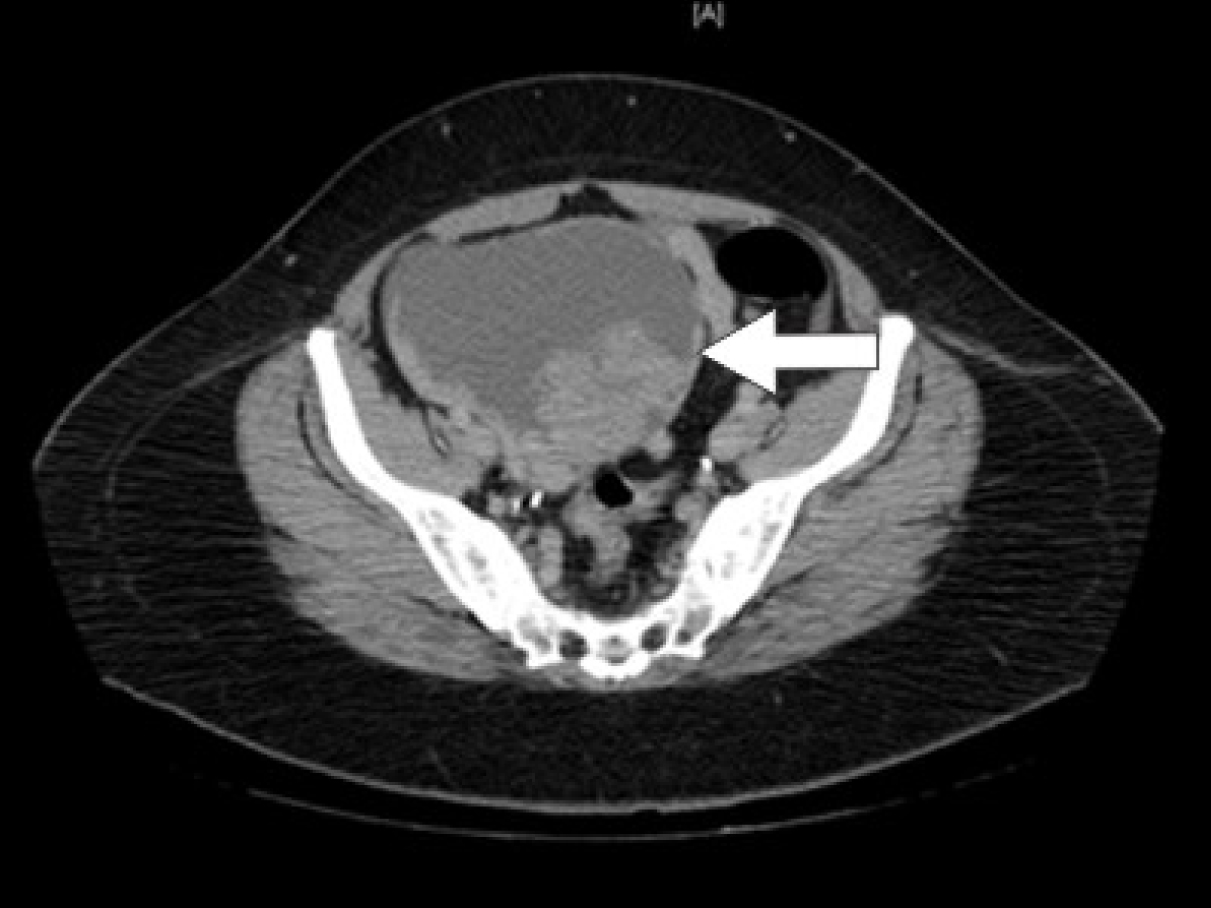

Initial laboratory studies were as follows: WBC 15.47 x 10/mcL, with a neutrophil count of 11.7 x 103/mcL; hemoglobin 13.3 gm/dL; platelet count 33 x 103/mcL; troponin 4.02 ng/mL; total CK 96 ng/mL, with a CK-MB 2.7 ng/mL and a relative index of 2.5; creatinine 0.8 mg/dL; international normalized ratio (INR) 1.56; PT 18.6 second; PTT 34.6 second; fibrinogen 209 mg/dL; fibrin degradation products (FDP) > 20 mcg/mL, and CA125 of 114 U/mL. Urinalysis showed moderate blood. Her EKG showed findings consistent with an acute, non-ST elevation myocardial infarction. CT imaging showed numerous large splenic, wedge-shaped hypodensities (Fig. 1) with similar areas in the kidneys bilaterally (Fig. 2), most consistent with infarcts. Also noted was a 12.4 x 8 x 11 cm right pelvic, complex, cystic and solid appearing mass (Fig. 3). An echocardiogram was obtained and showed mild mitral regurgitation and a moderate sized vegetation on the anterior mitral valve leaflet (Fig. 4). Lower extremity Duplex showed no apparent thrombosis.

![]() Click for large image | Figure 3. CT scan of the pelvis showing a 12.4 x 8 x 11 cm right pelvic, complex, cystic and solid appearing mass. |